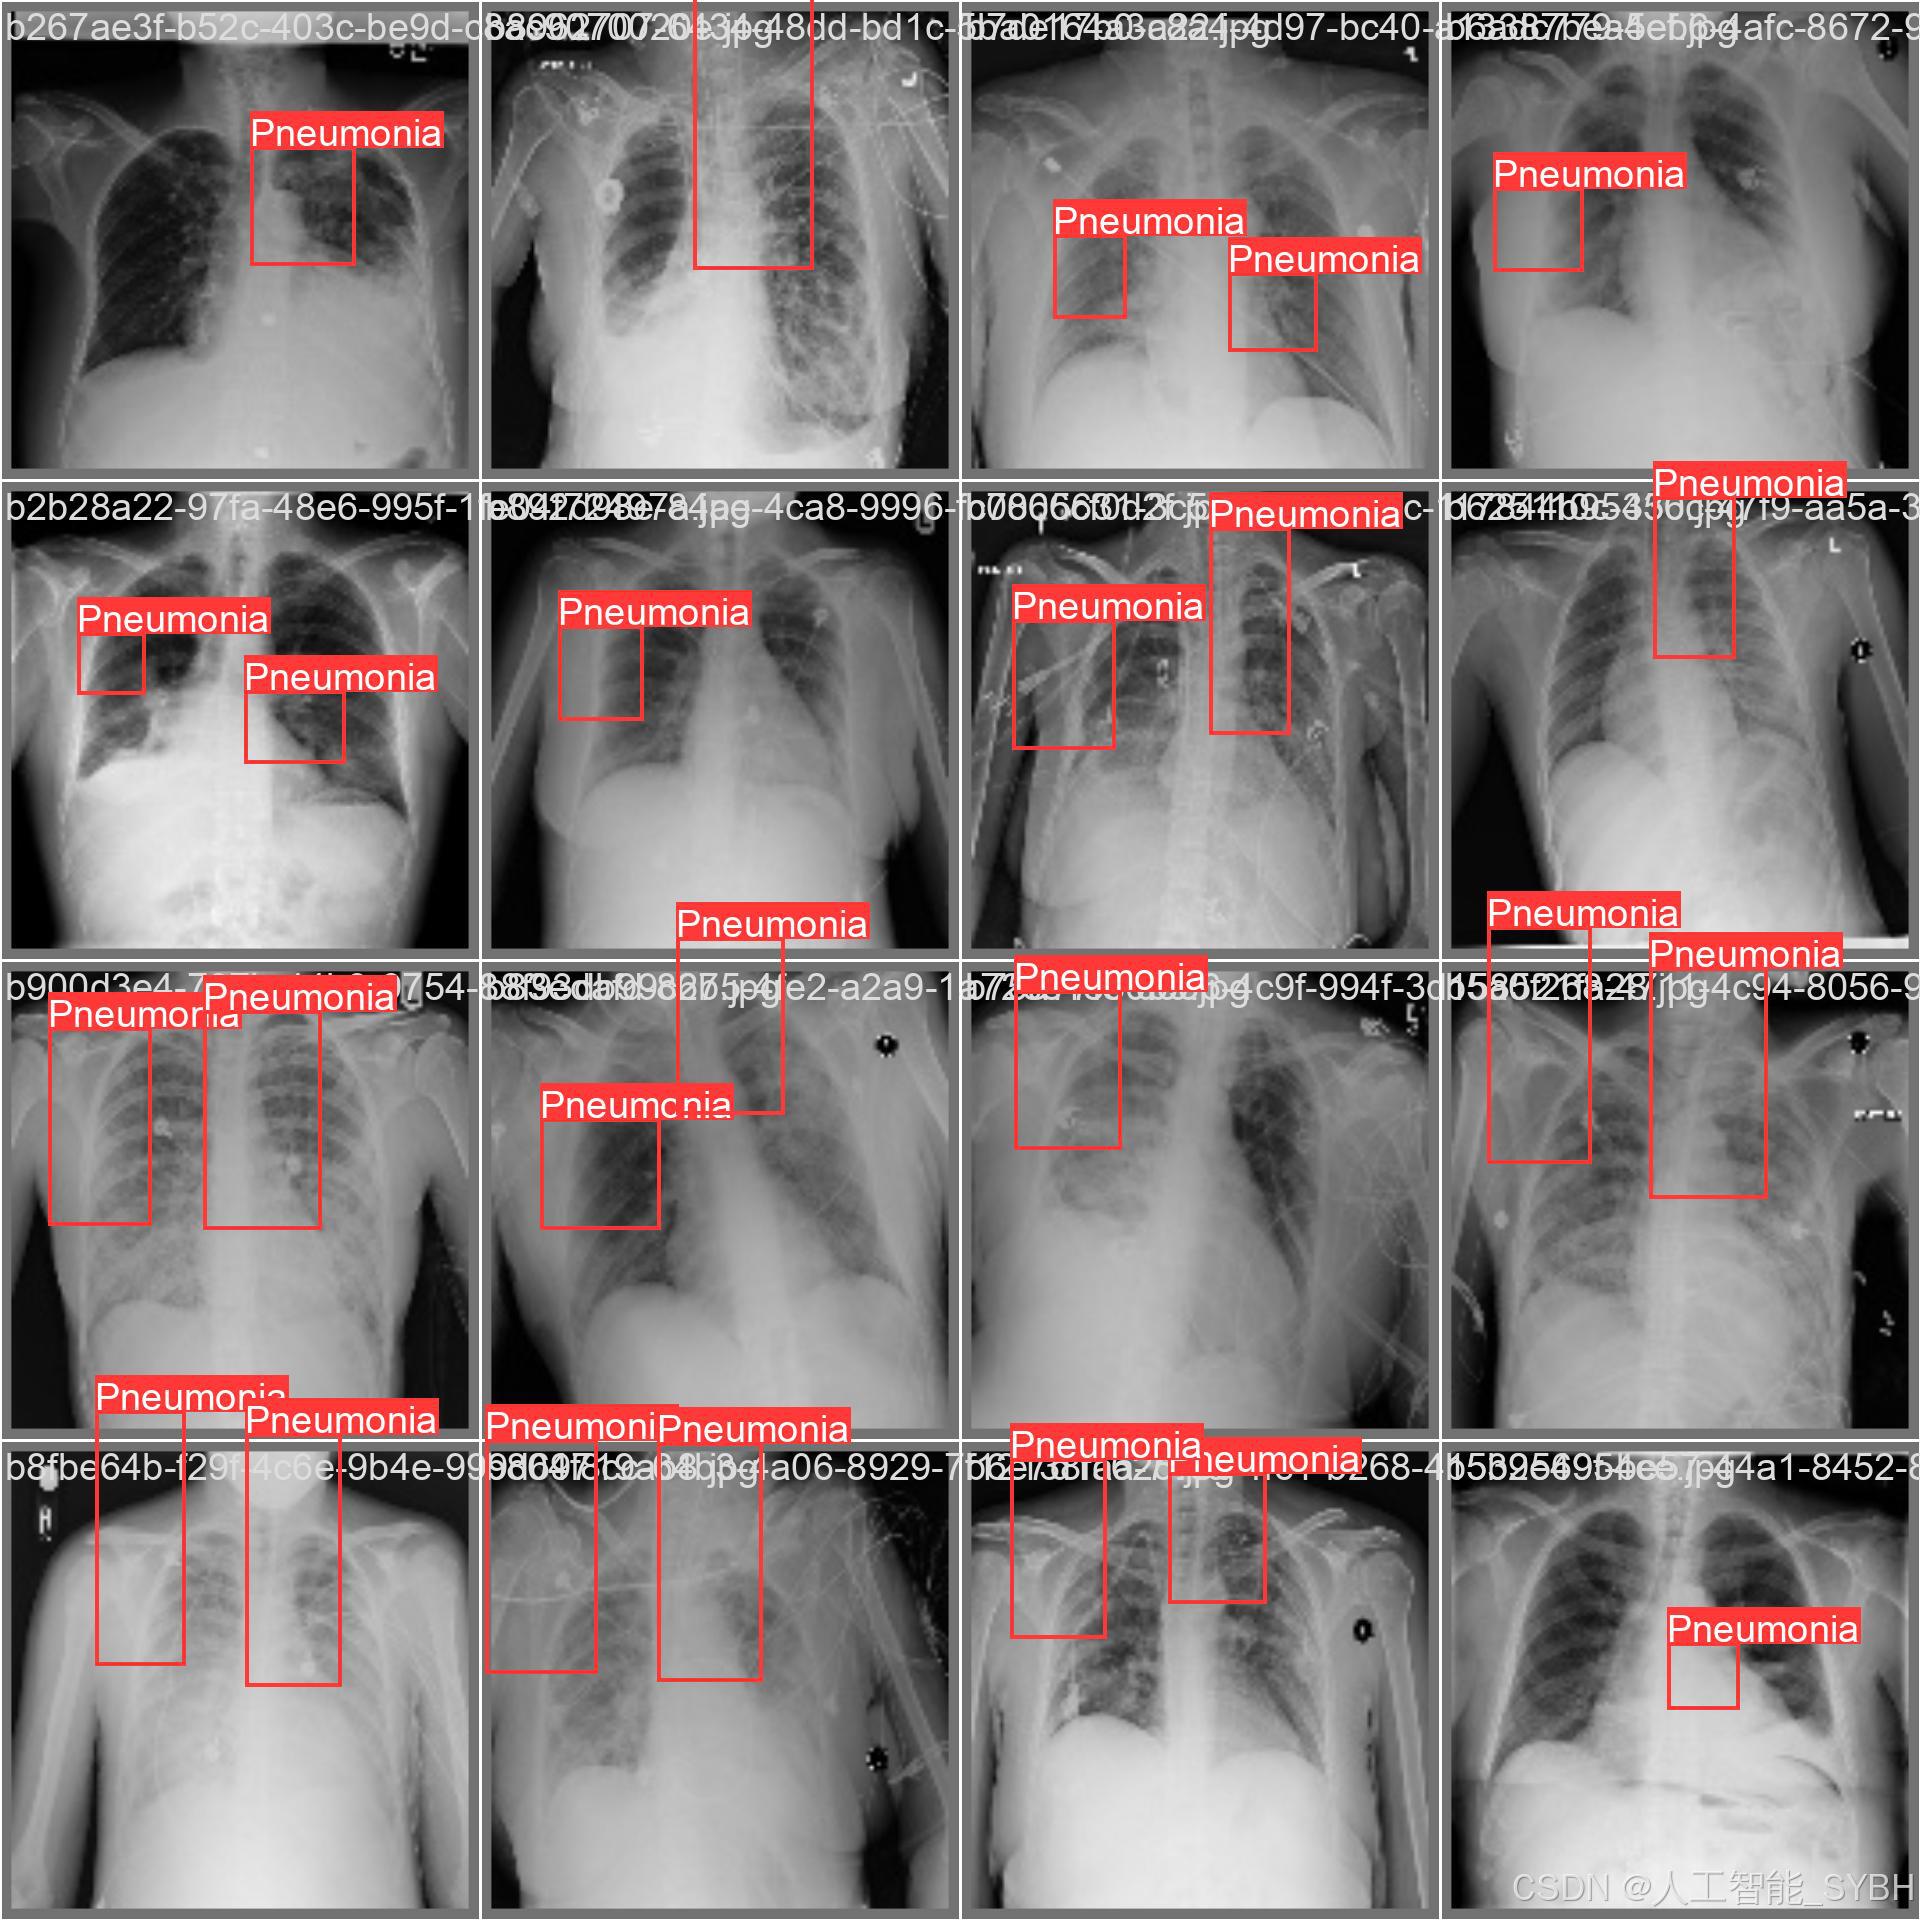

本项目基于YOLOv8深度学习框架,开发了一套高效、准确的肺炎智能检测系统,用于医学影像(如X光或CT扫描)中的肺炎识别。系统针对单类别('Pneumonia'肺炎)进行优化,采用包含3,772张训练图像、539张验证图像和1,078张测试图像的数据集进行训练和评估。该系统能够快速、自动地识别肺炎病变,辅助医生进行诊断,提高医疗检测效率,减少漏诊和误诊风险。

本项目基于YOLOv8深度学习框架,开发了一套高效、准确的肺炎智能检测系统,用于医学影像(如X光或CT扫描)中的肺炎识别。系统针对单类别('Pneumonia'肺炎)进行优化,采用包含3,772张训练图像、539张验证图像和1,078张测试图像的数据集进行训练和评估。该系统能够快速、自动地识别肺炎病变,辅助医生进行诊断,提高医疗检测效率,减少漏诊和误诊风险。

本系统利用计算机视觉和深度学习技术,实现了对肺炎影像的高精度检测,适用于临床辅助诊断、远程医疗筛查和大规模流行病监测等场景。相比传统人工阅片方式,该系统能够大幅缩短诊断时间,提高检测一致性,并降低医疗资源消耗,具有重要的临床应用价值。

数据集通过收集医院中的胸部X光片构建,涵盖了不同年龄段、性别和病情的患者,以确保模型的泛化能力。

每张图像中的肺炎区域均使用边界框(Bounding Box)标注,并标注对应的类别。